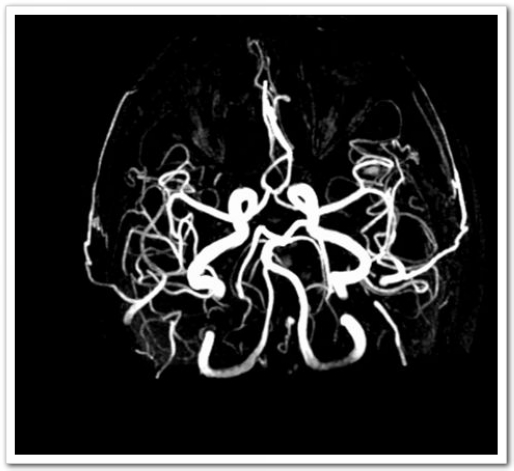

60岁的张阿姨这天正在家中看电视,突然感觉自己右侧上肢使不上劲,主要为右手拿不稳东西,日常生活动作突然不能像平时那样完成。真是人在家中坐,病从天上落,症状持续无明显缓解,也无进一步加重,遂至深圳大学总医院神经内科就诊。入院后头颅CT排除脑出血;颅脑磁共振平扫MRI+MRA:1.左侧顶叶皮层急性腔隙性梗死灶。2.双侧额、顶叶皮层下少许缺血灶。3.头颅MRA未见血管异常。

图2: MRA:未见异常